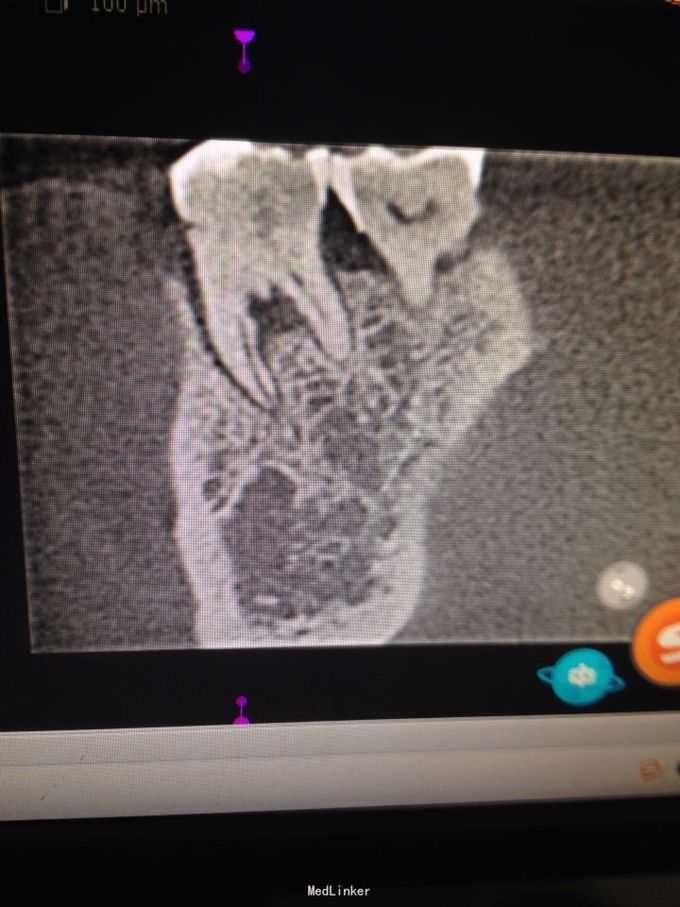

牙根纵折

慢性根尖周炎 慢性根尖周炎 根尖周炎

牙龈肿痛伴咬合疼一月余。一月前,突然发生右下牙齿疼痛,呈持续性,阵发性。期间自服消炎药,疼痛减轻。近这两周,再次疼痛,伴咬合疼,遂来诊。

右下六颊侧见窦道,积压见脓液溢出,扪疼明显,扣疼剧烈。牙冠完整,未见龋坏发生。

询问病史有咬硬物硌牙史。诊断:牙根纵折,慢性根尖周炎急性发作。 局麻下微创拔除。